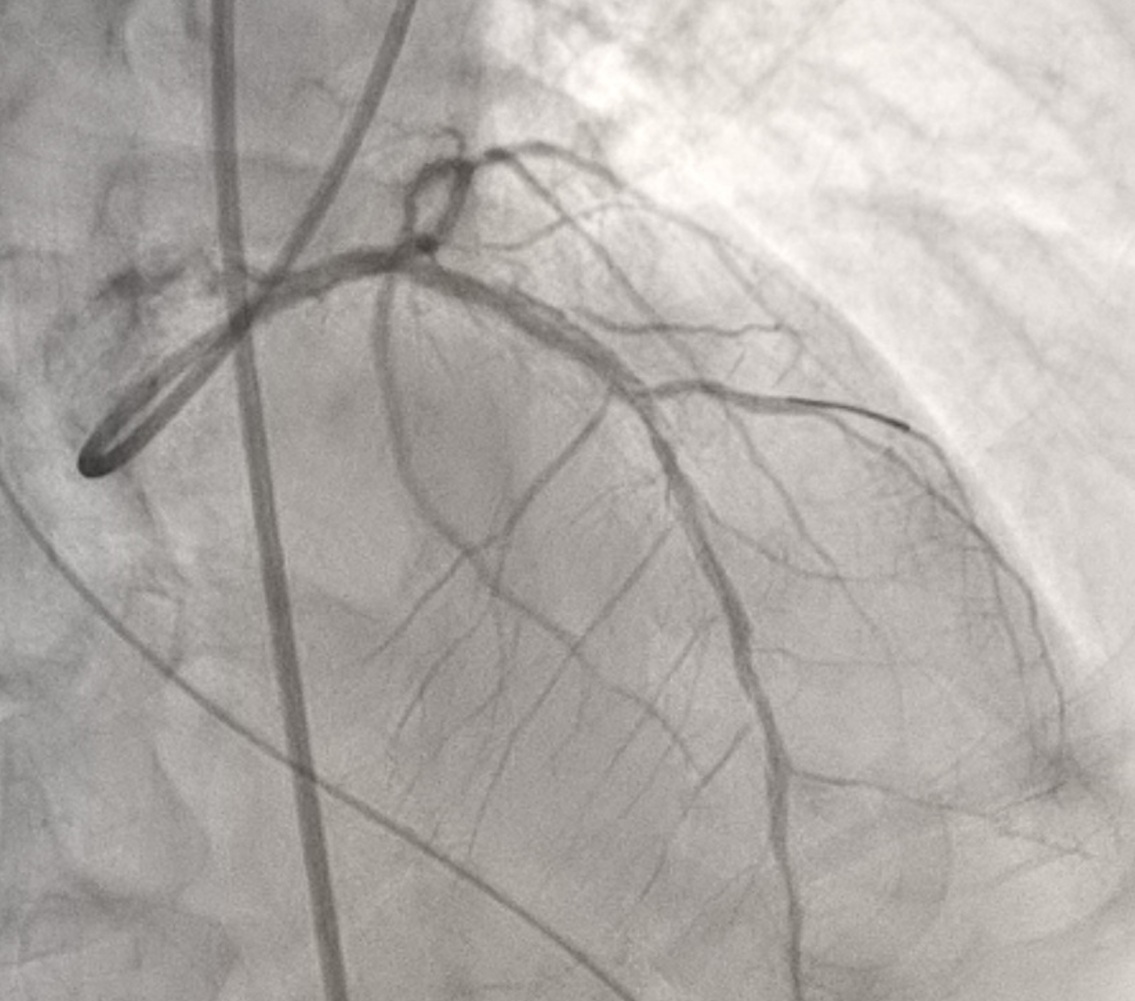

During the PCI, severe diffused lesion with maximum 95% stenosis around proximal part to distal part of LAD and 60% stenosis in the middle part of RCA were diagnosed.

A 3.5x7F ASAHI PB Guide catheter with Sion guidewire was provided for LAD revisualization.After placing the guidewire in LAD, series balloon were provided todilate the stenotic lesions as Figure 1 showed. A 2.5x38 mm stentwas applied to place the distal part lesion of LAD. However, the difficulty to movethe stent to the correct place due to length of the stent and the irregularlumen of proximal part of LAD. 6.0F extension microcatheter was used to assistthe stent moving and implanting. After stenting, the extension microcatheterwas entrapped around middle part of LAD as Figure 2 showed. After pullingbackwards forcedly, the fracture of proximal part of the microcatheter was detectedand previous guidewire was pull out from coronary artery. After rewiring into the distalpart of LAD via the lumen of the fractured microcatheter, 7.0F telescopemicrocatheter with a 2.5x15 mm balloon was applied. The balloon wasmoved in the position 2-3 mm inferior to the fractured microcatheter and proximalpart of telescopemicrocatheter was placed in the ostium of left main coronary artery. After theballoon inflated, the whole sets including the body of the balloon and thetelescope microcatheter were pull backwards. The fractured catheter was movedbackwards with the inflated balloon to enter the telescope microcatheter. Thewhole sets with the fractured catheter were retried from the patientsuccessfully. The retried balloon and fractured catheter were illustrated inFigure 3.